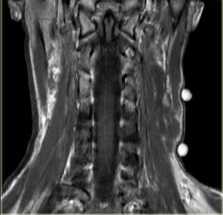

МРТ мягких тканей шеи. Корональная Т2-взвешенная МРТ. Невринома плечевого сплетения справа. Цветовая обработка изображения.

Плечевой сплетение состоит из тесно переплетающихся нервных стволов, отходящих от вентральных корешков нервов шейного отдела (С5-С7) и грудного отдела (Т1) спинного мозга. 3 первичных ствола неоднократно делятся и взаимно соединяются. Плечевое сплетение, в конечном итоге, переходит в нервы верхних конечностей, обеспечивая чувствительную и двигательную иннервацию. Расположено плечевой сплетение в области ключицы.